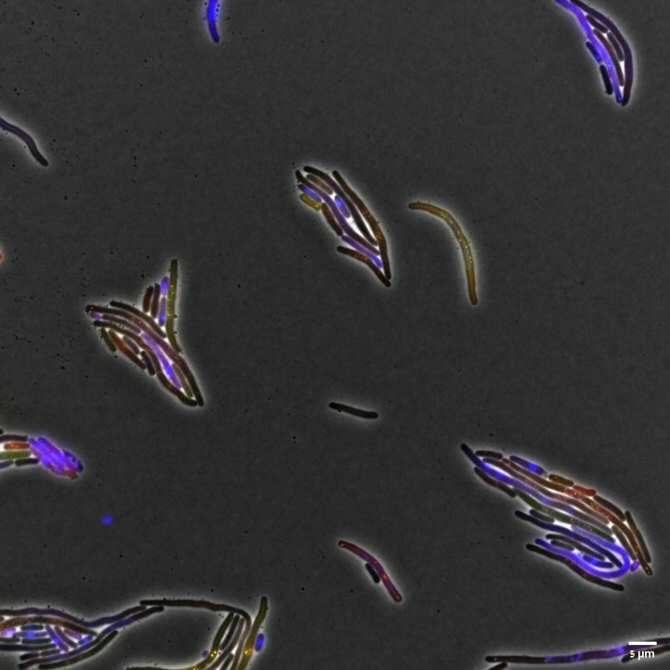

La elongación de las bacterias debido a la inhibición de la división celular (el modo en que se reproducen) es causada por la proteína saboteadora del virus bacteriófago. (Imagen: Tridib Mahata)

Estos científicos han descubierto un mecanismo por el que los virus "buenos" pueden atacar algunos sistemas vitales de las bacterias "malas", saboteando su normal funcionamiento y bloqueando su reproducción. Los investigadores han demostrado que el virus "bueno" (bacteriófago) es capaz de bloquear el mecanismo de replicación del ADN de la bacteria sin dañar el suyo propio.

Mahata, Qimron y sus colegas descubrieron que una proteína del bacteriófago investigado utiliza una proteína de reparación del ADN de la bacteria para cortar "astutamente" el ADN de la bacteria mientras se repara. En otras palabras, sabotea un mecanismo de la bacteria para que este cause destrozos en ella en vez de repararla. Como el ADN del bacteriófago no necesita esta proteína de reparación específica, está protegido de los efectos de este sabotaje. De este modo, el virus "bueno" hace tres cosas importantes: distingue entre su propio ADN y el de la bacteria, destruye el material genético de la bacteria y bloquea la división celular de la bacteria y por tanto su propagación.